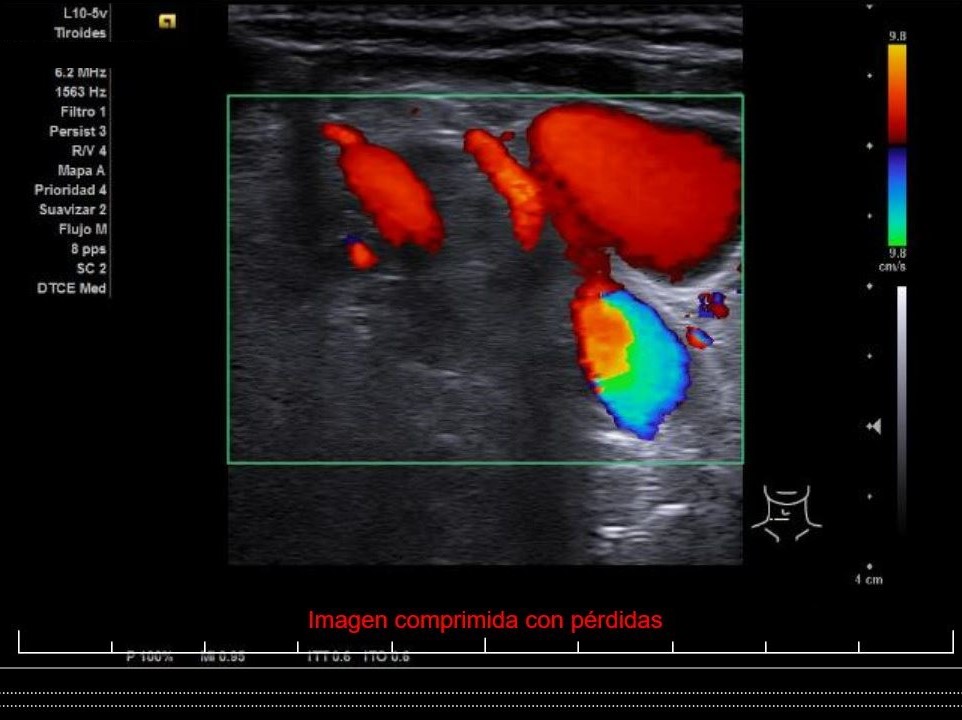

Se aprecia un tiroides de características ecográficas compatibles con tiroiditis, sin cambios respecto a ecografía previa, al igual que la grasa peritiroidea derecha, pero de manera incidental se observa un aumento del calibre fusiforme de la yugular externa derecha con respecto a la izquierda, con flujo vascular reducido.